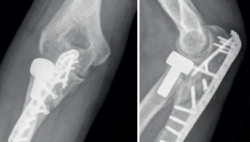

Figura 9. Imágenes radiológicas tras la reintervención en la que se retiró todo el material de osteosíntesis a través de un abordaje posterior del codo que permitió reducir y fijar el cúbito con una placa específica del olécranon y tornillos adicionales, la fractura de la coronoides con un tornillo de la placa, desde posterior a anterior, y la colocación de una prótesis de la cabeza del radio. Al finalizar la intervención se comprobó la reducción y la estabilidad de la articulación radiocubital proximal, pero el codo se subluxaba al colocar el antebrazo en supinación y flexión de 30°, por lo que durante las primeras 6 semanas se permitió la flexión libre del codo con el antebrazo en rotación neutra y se limitó la extensión a -30°.